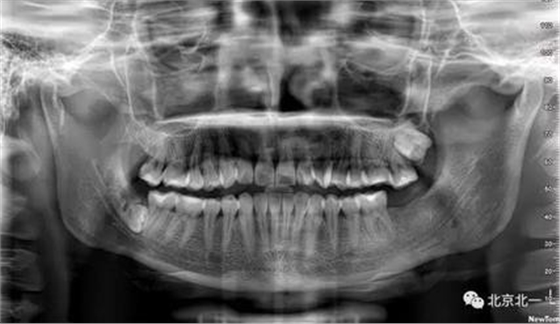

病例資料:一般情況,患者女性,28歲, 主訴:要求拔右側下頜智齒,檢查:右側下頜第三磨牙未見萌出, 拍片如圖。

圖一:CBCT顯示右側下頜水平骨埋伏牙,牙冠距離下牙槽神經管接近。